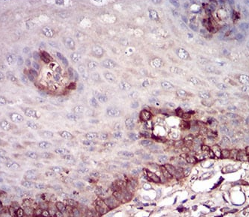

IHC    1/200 - 1/1000